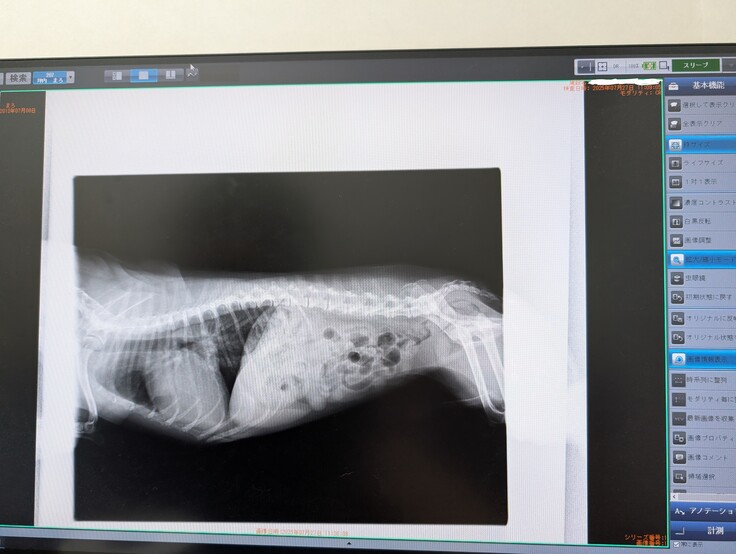

採血の心エコー検査の他にも、腹部エコーや心電図もやっております。

定期的に受診し薬の調整をしたが、心臓の拡大が認められる。

心臓の手術適応かどうかの検査を行う。検査の結果心臓以外の異常は見られず、先生からは現在ステージCであること、手術は今がベストであると説明を受ける。